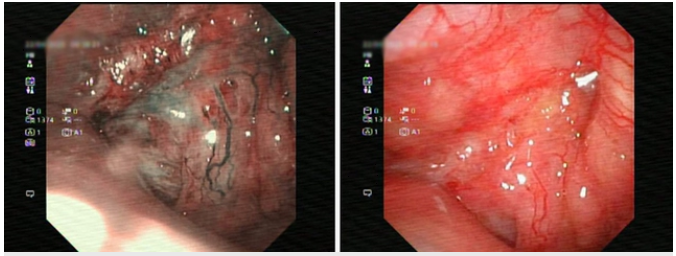

Nội soi phát hiện khối u ở ṿm họng. Ảnh: BVCC

Bệnh nhân được thăm khám và thực hiện các thăm ḍ cần thiết để đánh giá t́nh trạng sức khoẻ. H́nh ảnh cộng hưởng từ (MRI) cho thấy tổn thương thâm nhiễm vùng ṿm họng và thành hầu miệng bên phải, xâm lấn xương nền sọ, thành xoang bướm phải và lan đến vùng lỗ mũi sau phải. Ghi nhận thêm một nốt ngấm thuốc tại xương trán phải, cần loại trừ tổn thương ác tính. Đồng thời phát hiện nhiều hạch nhỏ vùng dưới cằm và hai bên góc hàm.

Kết quả giải phẫu bệnh từ mẫu sinh thiết ṿm họng xác định đây là ung thư biểu mô vảy không sừng hóa, loại mất biệt hóa – một thể ác tính cao.